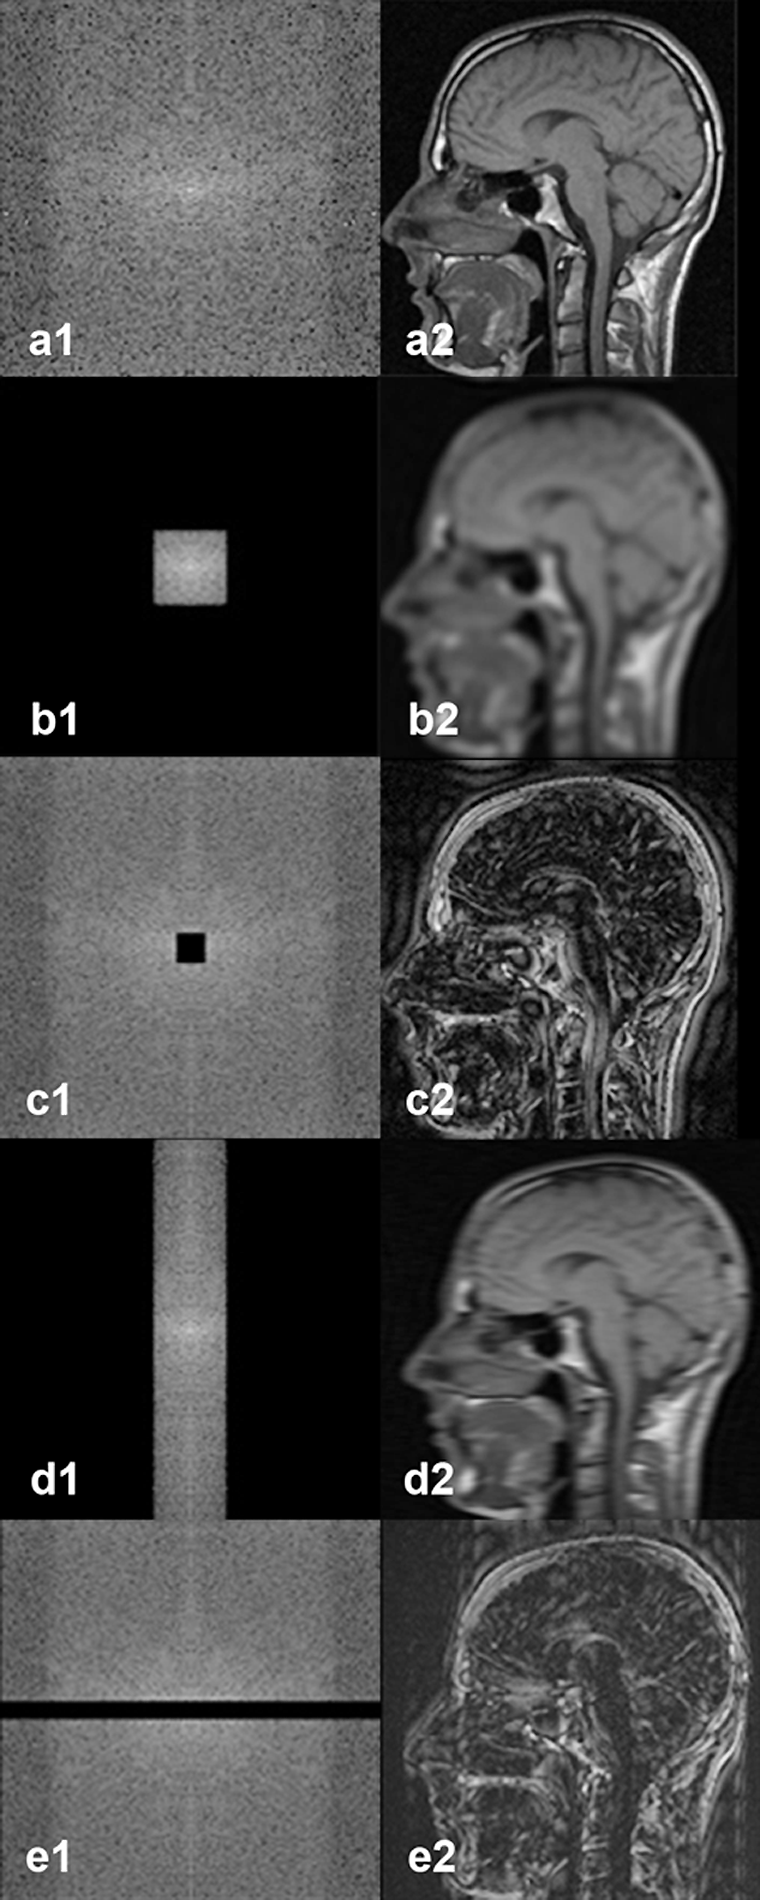

Figura 07-07:

k-Space with spatial frequency filtering.

a1|a2: Regular k-space with image re­con­struc­tion.

b1|b2: Same k-space as in (a) with filtering of the high frequencies; the reconstructed image has lost sharpness, it looks blurred, yet image contrast has hardly been affected.

c1|c2: Spatial frequency fil­te­ring of the low frequencies; the re­con­struc­ted image has lost image contrast, but image details have hardly been affected.

d1|d2: Low pass filtering in the readout direction, …

e1|e2: … high pass filtering in the preparation direction.